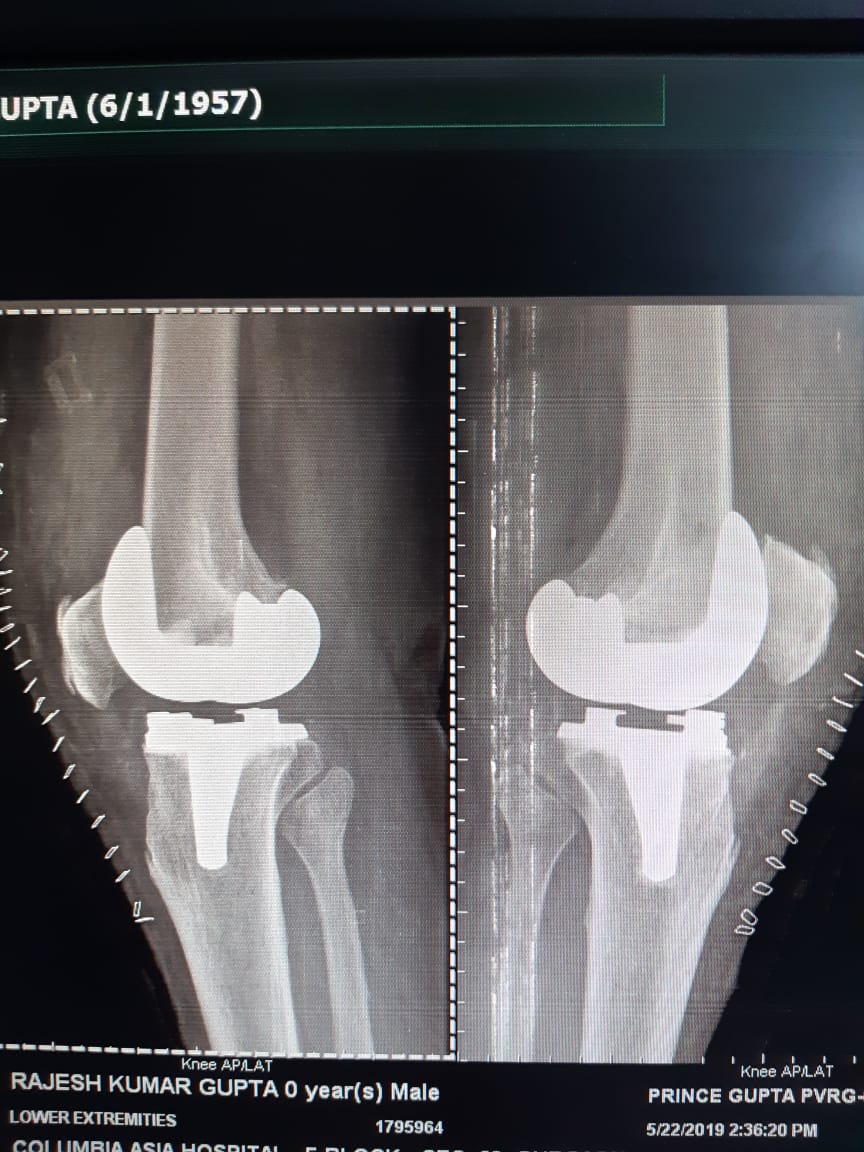

Case I: This is a case of bilateral total knee replacement

Important point is that patient started walking with walker the very next day. At the time of discharge he was walking with stick on 4th day